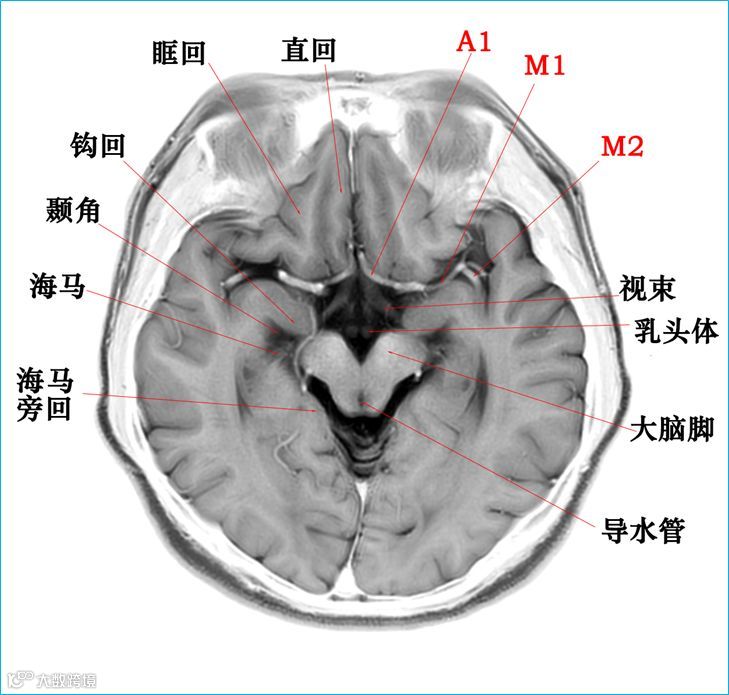

在T2WI反相图学下的颅脑断层解剖(吴晓安老师亲自手动标准)以及标本断层解剖,满满干货,坐在小板凳上,一起学习吧……